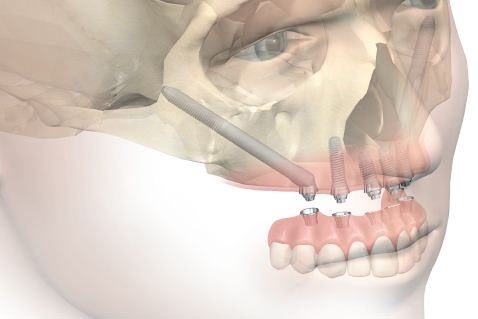

W sytuacji, gdy wraz z bezzębiem mamy do czynienia z trudnymi bądź niemożliwymi dla konwencjonalnej implantologii warunkami kostnymi w zakresie szczęk, rozwiązaniem są implanty jarzmowe Zygoma. Przeznaczone są dla pacjentów, u których dotychczas kwestionowano w ogóle możliwość wykonania zabiegów implantologicznych.

Są dużo dłuższe od typowych implantów i występują w długościach od 30 do 52,5 mm, aby w sytuacji braku kości w strefie części zębodołowej mogły dotrzeć i być mocno ustabilizowane w trzonie kości jarzmowej, znajdującej się w odległości kilku centymetrów od pozycji zębów.

Klasyczny implant Zygoma ma zróżnicowaną szerokość trzonu: 4,5 mm – 1/3 górnej i 4 mm – 2/3 dolnej, która uwzględnia optymalne jego mocowanie zarówno w zanikłej kości szczęki u dołu, jak i mocnej strukturze kości jarzmowej u góry, która jest w tych przypadkach podstawą w stabilizacji implantu. Dzięki jej budowie ta unikalna koncepcja lecznicza daje podstawy natychmiastowej odbudowy protetycznej uzębienia oraz stabilnych i długoterminowych efektów leczenia.

Istotna różnica w budowie w stosunku do tradycyjnych implantów to kąt główki, który wynosi 45° oraz 0°.

Koncepcja 45° wynika ze skośnej pozycji implantu mocowanego w zatoce szczękowej i trzonie kości jarzmowej, tak aby uprościć i zoptymalizować rozwiązania protetyczne.

Koncepcja 0° uwzględnia uproszczenie chirurgicznej części procedury, natomiast protetyczna część optymalizowana jest dzięki użyciu specjalnych łączników kątowych MultiUnit – jak w technice All-on-4.

2 implanty jarzmowe, 2 lub 4 krótkie implanty korzeniowe, 4 lub 6 łączników MultiUnit, natychmiastowy tymczasowy most wykonany z akrylu, o ile jest to możliwe.

4 implanty jarzmowe, 4 łączniki MultiUnit, natychmiastowy tymczasowy most wykonany z akrylu o ile jest to możliwe.

Implant zygomatyczny Zygoma, nazywany też jarzmowym, jest wszczepem śrubowym zbudowanym z tytanu, tak jak standardowe implanty. Od tradycyjnych wszczepów różni go kształt, długość oraz przeznaczenie. Jest implantem mniej uniwersalnym, używa się go tylko w zakresie szczęk, czyli górnego łuku. Zazwyczaj wprowadza się go w odcinku bocznym bezzębnej szczęki i zakotwicza w trzonie kości jarzmowej pod kątem 45 stopni w stosunku do płaszczyzny zgryzu; używana w medycynie łacińska nazwa kości jarzmowej to os zygomaticum, stąd też nazwa implantu – Zygoma.

Unikalna konstrukcja implantu Zygoma umożliwia jego stabilne kotwiczenie w trudnych i skrajnie trudnych warunkach kostnych bezzębnych szczęk. Dobre mocowanie implantu jarzmowego powodowane jest jego penetracją przez mocną strukturę kości jarzmowej, która doskonale stabilizuje wszczep. Daje to możliwość szybkiej rehabilitacji protetycznej u bezzębnych pacjentów, gdzie odbudowa protetyczna uzębienia w formie stabilnych mostów nie byłaby możliwa przy użyciu tradycyjnych, krótkich implantów zębowych. Przywraca pacjentowi w pełni funkcję żucia i egzystencję bez protez ruchomych.

O ilości wszczepionych implantów Zygoma decydują warunki kostne szczęk pacjenta. W sytuacji braku wystarczającej ilości kości w odcinkach bocznych, czyli w okolicy zębów przedtrzonowych i trzonowych, oraz przy wystarczającej jej ilości w odcinku przednim podnosowym, wszczepia się pojedyncze implanty zygomatyczne – symetrycznie po obu stronach oraz 4 lub 2 tradycyjne, krótkie implanty zębowe w odcinku przednim.